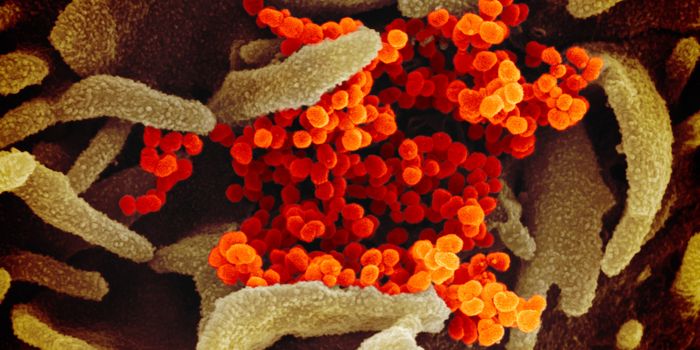

MAY 10, 2021MicrobiologyThe pandemic virus SARS-CoV-2 has changed the world in devastating ways, taking hundreds of thousands of lives & new var ...